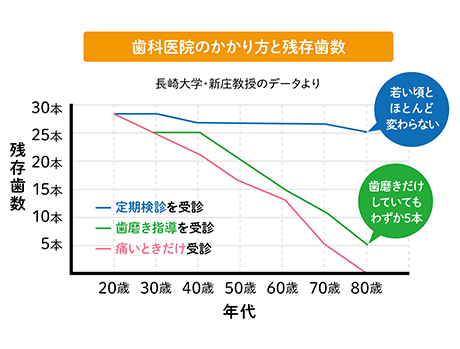

クリーニングなど定期的な口腔ケアを行うことで口腔内トラブルの減少につながります。

治療を繰り返すと歯がダメージを受けて寿命が縮みますが、予防することで大切な歯を健康な状態のまま保つことができるようになります。

定期的なメンテナンスを行うことで症状が進んでしまう前に発見・治療が可能になります。

その結果、早期治療で治療期間も短く済むため費用を抑えることもできます。

歯科先進国のスウェーデンでは、国民の80~90%が定期的な歯科検診を受けています。 80歳以上でも定期検診を受けることで平均20本の歯が残っているというデータもあります。定期的にメンテナンスを行い、むし歯や歯周病を予防することは健康な歯を残していくためにとても重要です。